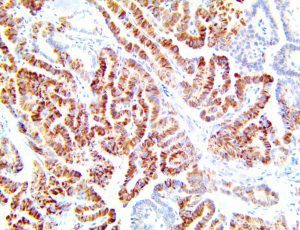

The first cytokines released are interleukin 1β (IL-1β) and tumor necrosis factor-α (TNF-α), which attract a variety of circulating white blood cells (WBCs) to the infection site, including neutrophils, monocytes, macrophages, and natural killer (NK) cells. This response, along with the antipathogenic chemicals released by these cells (i.e., complement), comprise the innate immune response. These cells directly attack the invading pathogen and also release additional cytokines, chief among them interleukin-1 and 6 (IL-6). IL-6 is essential for invoking the adaptive immune response, which calls T-cells, B-cells, and T helper (Th) cells to the infection site. IL-6 also stimulates further recruitment, proliferation and activation of macrophages.

It is the ICU physician who is most likely to witness one of the deadliest manifestations of the abnormal immunological response, the cytokine storm syndrome (CSS). This response is also referred to by some as the cytokine release syndrome (CRS). CSS is characterized by continuous activation and expansion of macrophage and lymphocyte populations, which secrete large amounts of cytokines, causing the cytokine storm. This massive cytokine release is akin to hemophagocytic lymphohistiocytosis (HLH) disease, a syndrome characterized by initial unchecked and persistent activation of cytotoxic T lymphocytes and NK cells.

This activation induces inflammatory monocytes to highly express IL-6, starting a localized and then systemic cascade effect that results in hyperproduction of IL-6, which accelerates the inflammatory process. Because IL-6 also increases vascular permeability, excessive levels cause blood vessels to become very leaky. This, along with clotting factors released from vascular endothelial cells, stimulates the coagulation cascade, resulting in microthrombosis (tiny clots), which leads to ischemia and tissue death of the kidney, intestines, heart, liver, brain and extremities.